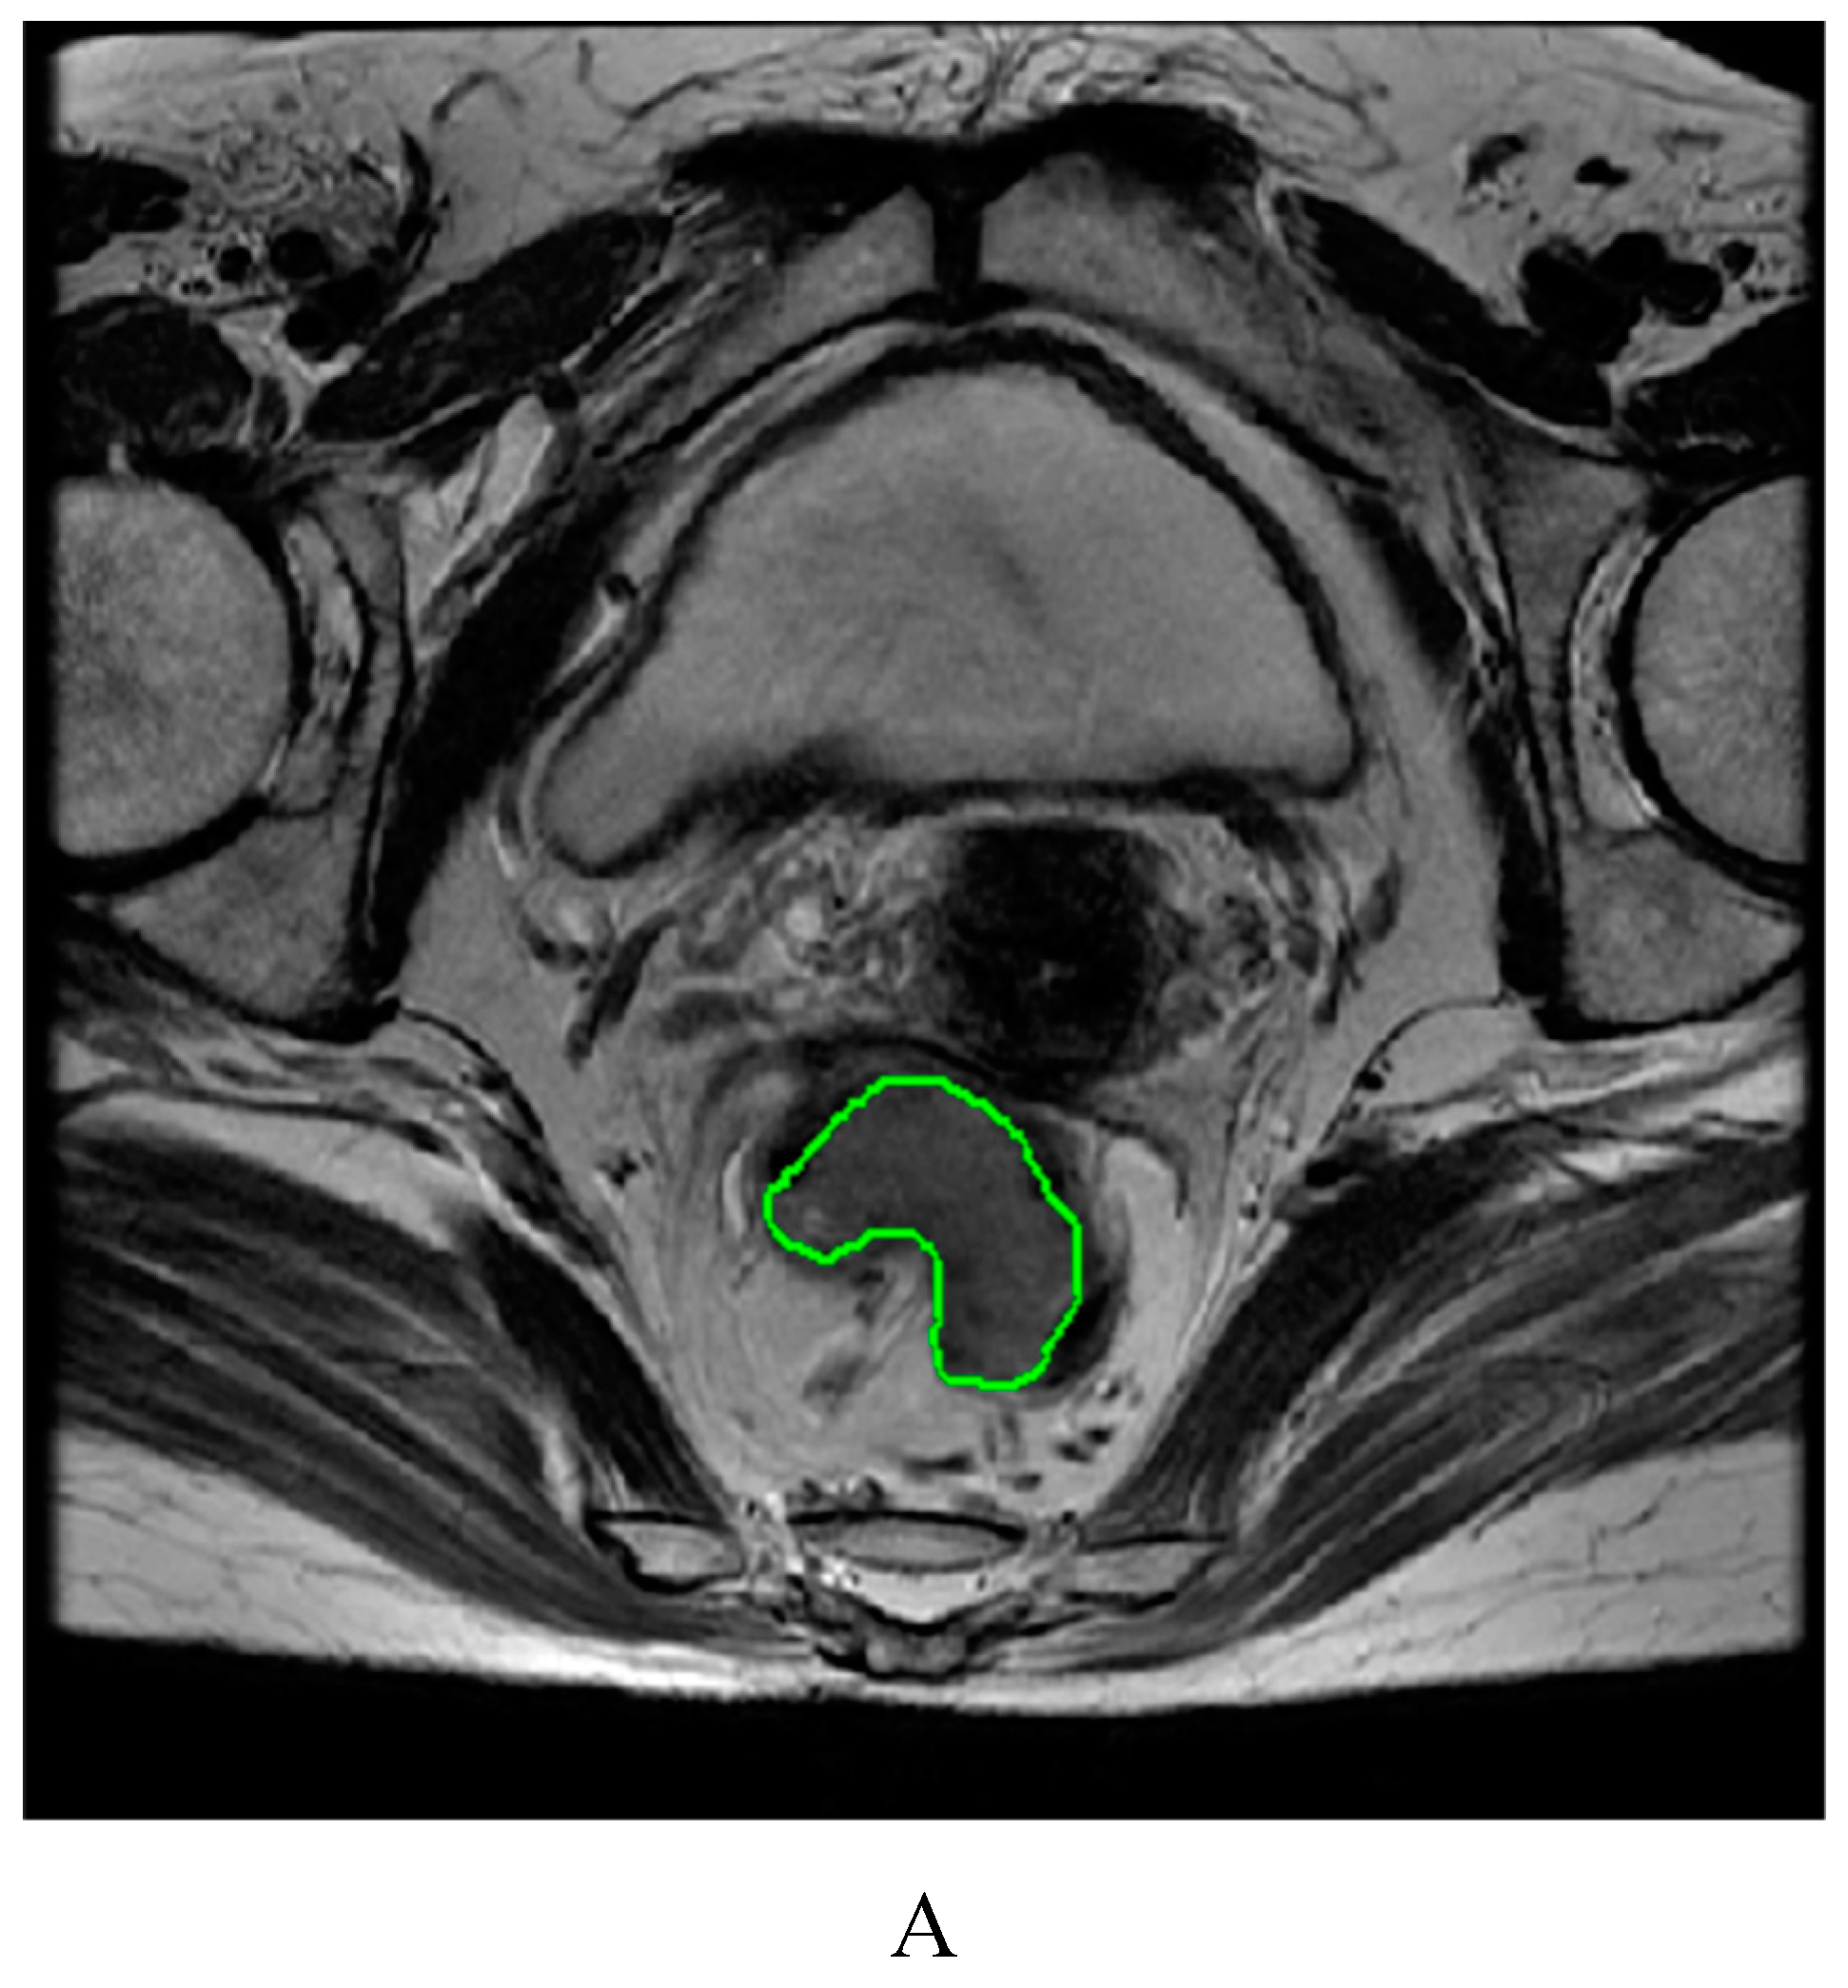

4.3. Image segmentation and feature extraction

| (oblique) axial T2WI | 1700-5050/110-120 | 4-6 | 320-384×256 | 200-360×200-360 | 90 |